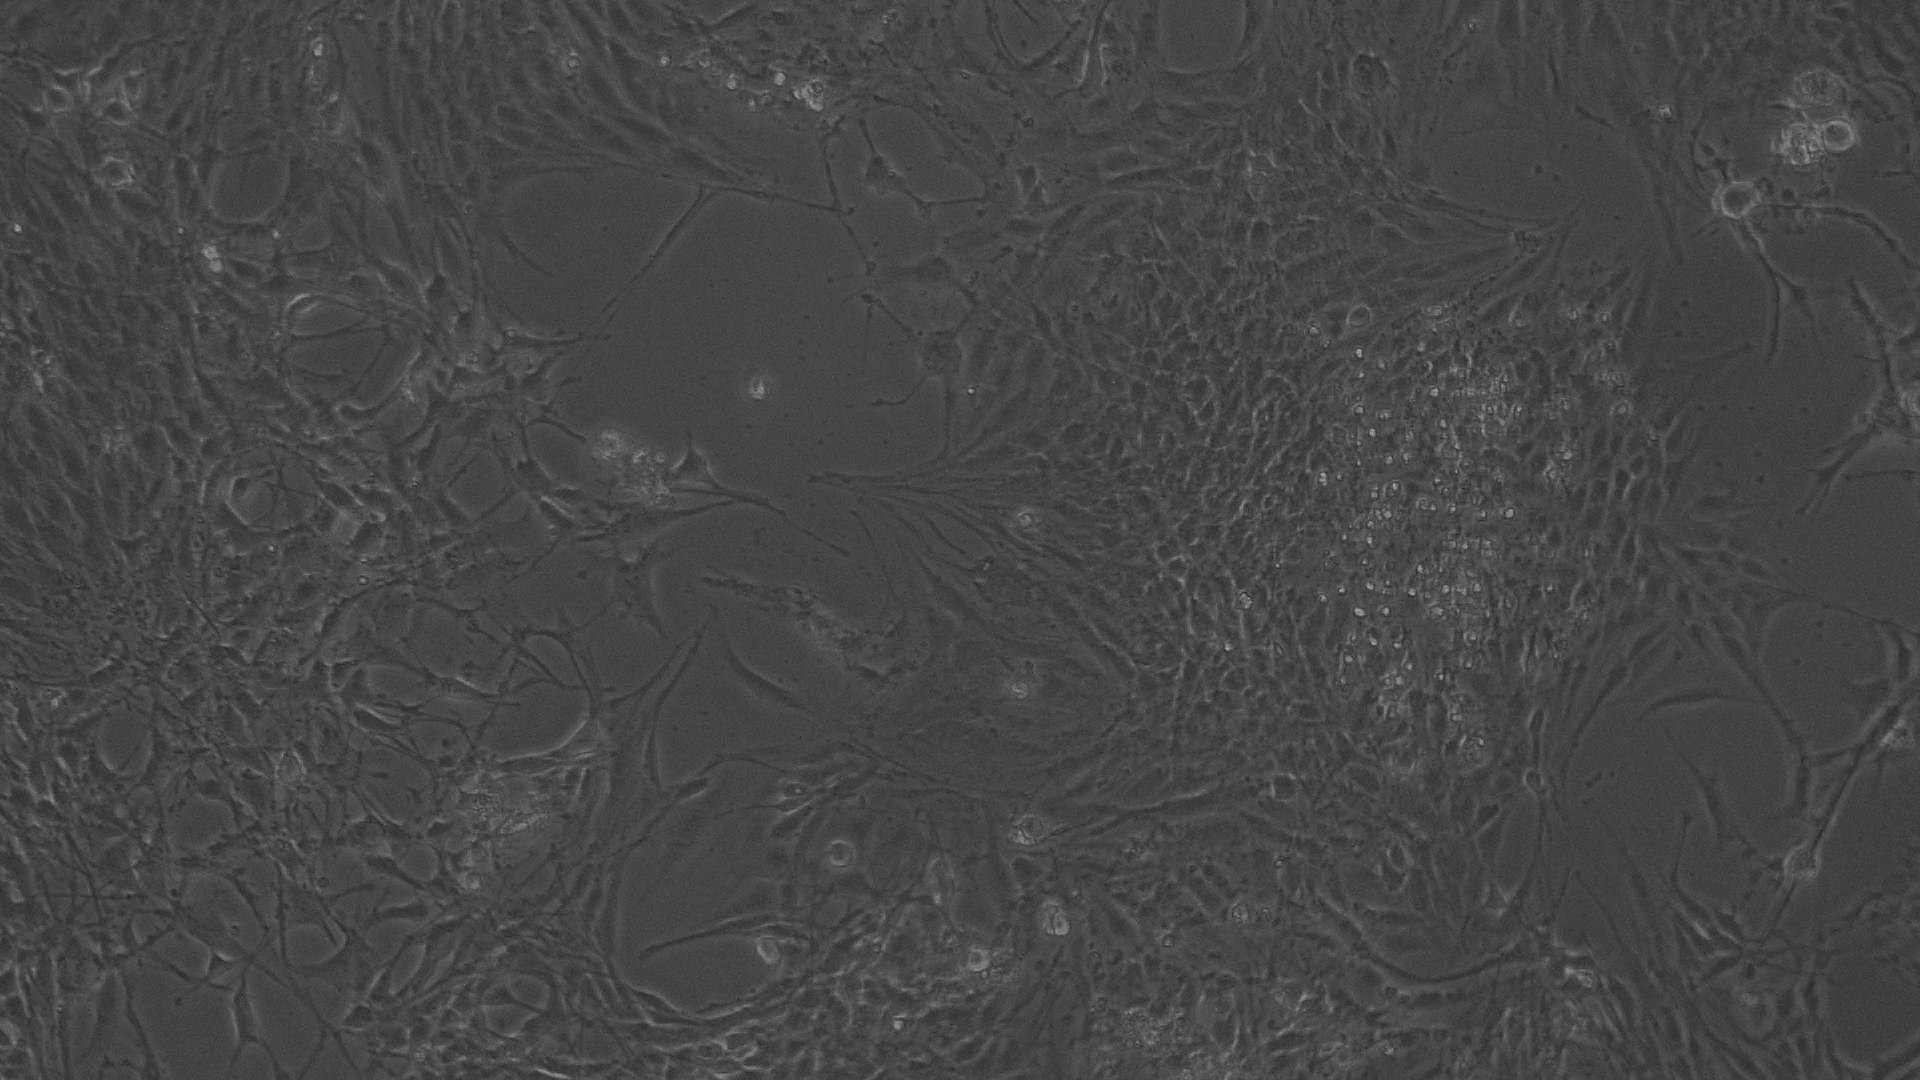

Antiproliferative effect by direct microscopic observation

The entire plate was observed at an interval of every 24 h; up to 72 h in an inverted phase-contrast tissue culture microscope (Labomed TCM-400 with MICAPSTM HD camera) and microscopic observations were recorded as images. Any detectable change in the morphology of the cells, such as rounding or shrinking of cells, granulation, and vacuolization in the cytoplasm of the cells, were considered as indicators of cytotoxicity.

In vitro anti-cancer activity

In vitro anticancer actiivity of ethanolic extract of leaves of Pothos scandens Linn. was evaluated against HeLa and MCF 7 cell lines. The viability of cells was evaluated by direct observation of cells by an Inverted phase contrast microscope and MTT assay method. The morphological changes in HeLa and MCF 7 cells after treatment with the extract and standard doxorubicin are shown in fig. 5, 6, 7 and 8. The IC50 values are shown in table 4.

According to the American National Cancer Institute (NCI), crude extracts with an IC50<30 μg/ml are considered to be active against cancer cells [32, 33]. Different concentrations of the ethanolic extract of leaves of Pothos scandens Linn. exhibited potent cytotoxic activity against HeLa and MCF 7 cell lines with IC50 of 22.9 and 18.32 μg/ml, respectively.

Fig. 6: Morphological changes showing inhibition of Hela cell lines by different concentrations of standard drug Doxorubicin. a: -ve control (95% ethanol), b: 0.097 µg/ml, c: 0.19µg/ml, d: 0.39 µg/ml, e: 0.78 µg/ml f: 1.56 µg/ml

Fig. 8: Morphological changes showing inhibition of MCF 7 cell lines by different concentrations of standard drug Doxorubicin. a: -ve control (95% ethanol), b: 0.097 µg/ml, c: 0.19µg/ml, d: 0.39 µg/ml, e: 0.78 µg/ml f: 1.56 µg/ml